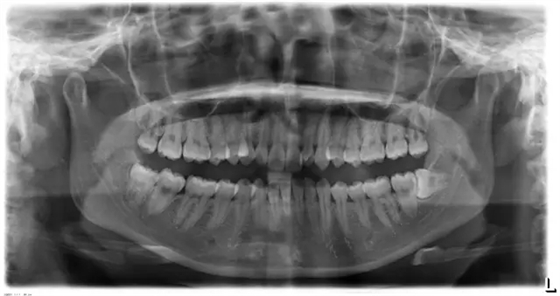

患者側(cè)面凸,鼻唇角較銳,笑時(shí)露齦笑明顯上下牙列擁擠,磨牙尖牙Ⅱ 類關(guān)系,3 度的深覆牙合,上頜中切牙伸長內(nèi)傾拔除上頜雙側(cè)的第一前磨牙,先粘上頜高轉(zhuǎn)矩的自鎖托槽排齊牙列,唇向開展上頜切牙,有一定的覆蓋,粘下頜標(biāo)準(zhǔn)轉(zhuǎn)矩托槽,上頜 1, 2 之間植入種植支抗壓入,同時(shí)后牙 5, 6 之間植入種植支抗內(nèi)收前牙,打開咬合關(guān)閉間隙。治療關(guān)鍵:前牙轉(zhuǎn)矩的控制第 1 個(gè)月 上頜粘上 Damon Q 高轉(zhuǎn)矩托槽,上 .014 熱激活 NiTi 絲。第 3 個(gè)月 上換 .014 x .025 熱激活 NiTi 絲。第 5 個(gè)月 上頜基本排齊,覆蓋增大,上換 .017 x .025 NiTi絲,下頜粘托槽,下 .014 熱激活 NiTi 絲。第 7 個(gè)月 上 .017 x .025 NiTi 絲加搖椅,下?lián)Q .014 x .025 熱激活 NiTi 絲第 9 個(gè)月 上頜換 .019 x .025 NiTi 絲加搖椅,下頜換 .017 x .025 NiTi 絲第 11 個(gè)月 下頜換 .019 x .025 加搖椅,上頜 1, 2 之間, 5, 6 之間植入種植釘,下頜出現(xiàn)散隙。第 13 個(gè)月 上頜換 .019 x .025ss 加搖椅,前牙種植釘用 Power Chain 壓低前牙(每側(cè) 100g),后牙種植釘關(guān)閉間隙(每側(cè) 150g),下?lián)Q .019 x .025ss,Power Chain 關(guān)閉間隙。第 19 個(gè)月 上頜前牙基本壓低到位去除前牙種植釘,繼續(xù)用關(guān)閉間隙,下頜散隙關(guān)閉。

第 22 個(gè)月 上頜覆蓋變小,去除 5, 6 之間種植釘,后牙前移關(guān)閉間隙。第 30 個(gè)月 患者未配合中線牽引,下中線仍有 1mm 右偏,患者對矯治效果滿意要求拆除,拆除固定矯治器,取模制作壓模保持器。 1.骨性 Ⅱ 類的患者內(nèi)收前牙時(shí)需對上頜前牙的轉(zhuǎn)矩進(jìn)行較好的控制才能獲得良好的面型和唇部形態(tài)。 2.露齦笑的患者治療前要分析其病因是唇、牙齦、牙齒、牙槽骨、上頜骨或多種因素結(jié)合,再制定矯治方案。 3.Ⅱ 類第二分類伴露齦笑的患者的上頜前牙移動軌跡是唇向開展-壓低-整體內(nèi)收。 4.Ⅱ 類第二分類牙齒舌傾比較厲害的情況,上頜中切牙慎用樹脂咬合墊。 5.壓低前牙或控根移動時(shí)容易發(fā)生牙根的吸收,需輕力緩慢的移動。